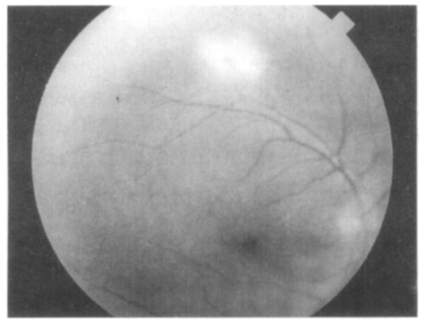

On December 15, 1997, a 60-year-old man visited out-patient clinic at the Department of Ophthalmology, Catholic University of Korea, College of Medicine, due to a decreased and blurred vision in his right eye which persisted for 2 weeks with slight muscle pain. He had no other previous problems with his general health, but he had been treated with oral antihypertensive drugs for 5 years. With a slit-lamp examination, mild inflammatory reaction was detected in the anterior chamber and vitreous body. Through an ophthalmoscopy, one optic disk-sized whitish retinal infiltration was observed in the superior temporal vascular area. One percent of prednisolone acetate (O-LON) solution was applied topically for 10 days (4 times/day). However, retinal infiltration continued to progress and sheath perivascularly on ophthalmoscopy, and hypofluorescent retinal area was detected on a fluorescein angiography. Retinal necrosis was suspected, thus 40 mg of prednisolone (H-LON) was orally administered 3 times a day. Two weeks later, the fundus examination of the right eye showed aggravated inflammation and retinal necrosis as shown in Fig. 1. Oral administration of prednisolone was terminated.

Fig. 1

The fundus of the patient before chemotherapy showing diffuse lesion of inflammation.

Fig. 1 The fundus of the patient before chemotherapy showing diffuse lesion of inflammation.